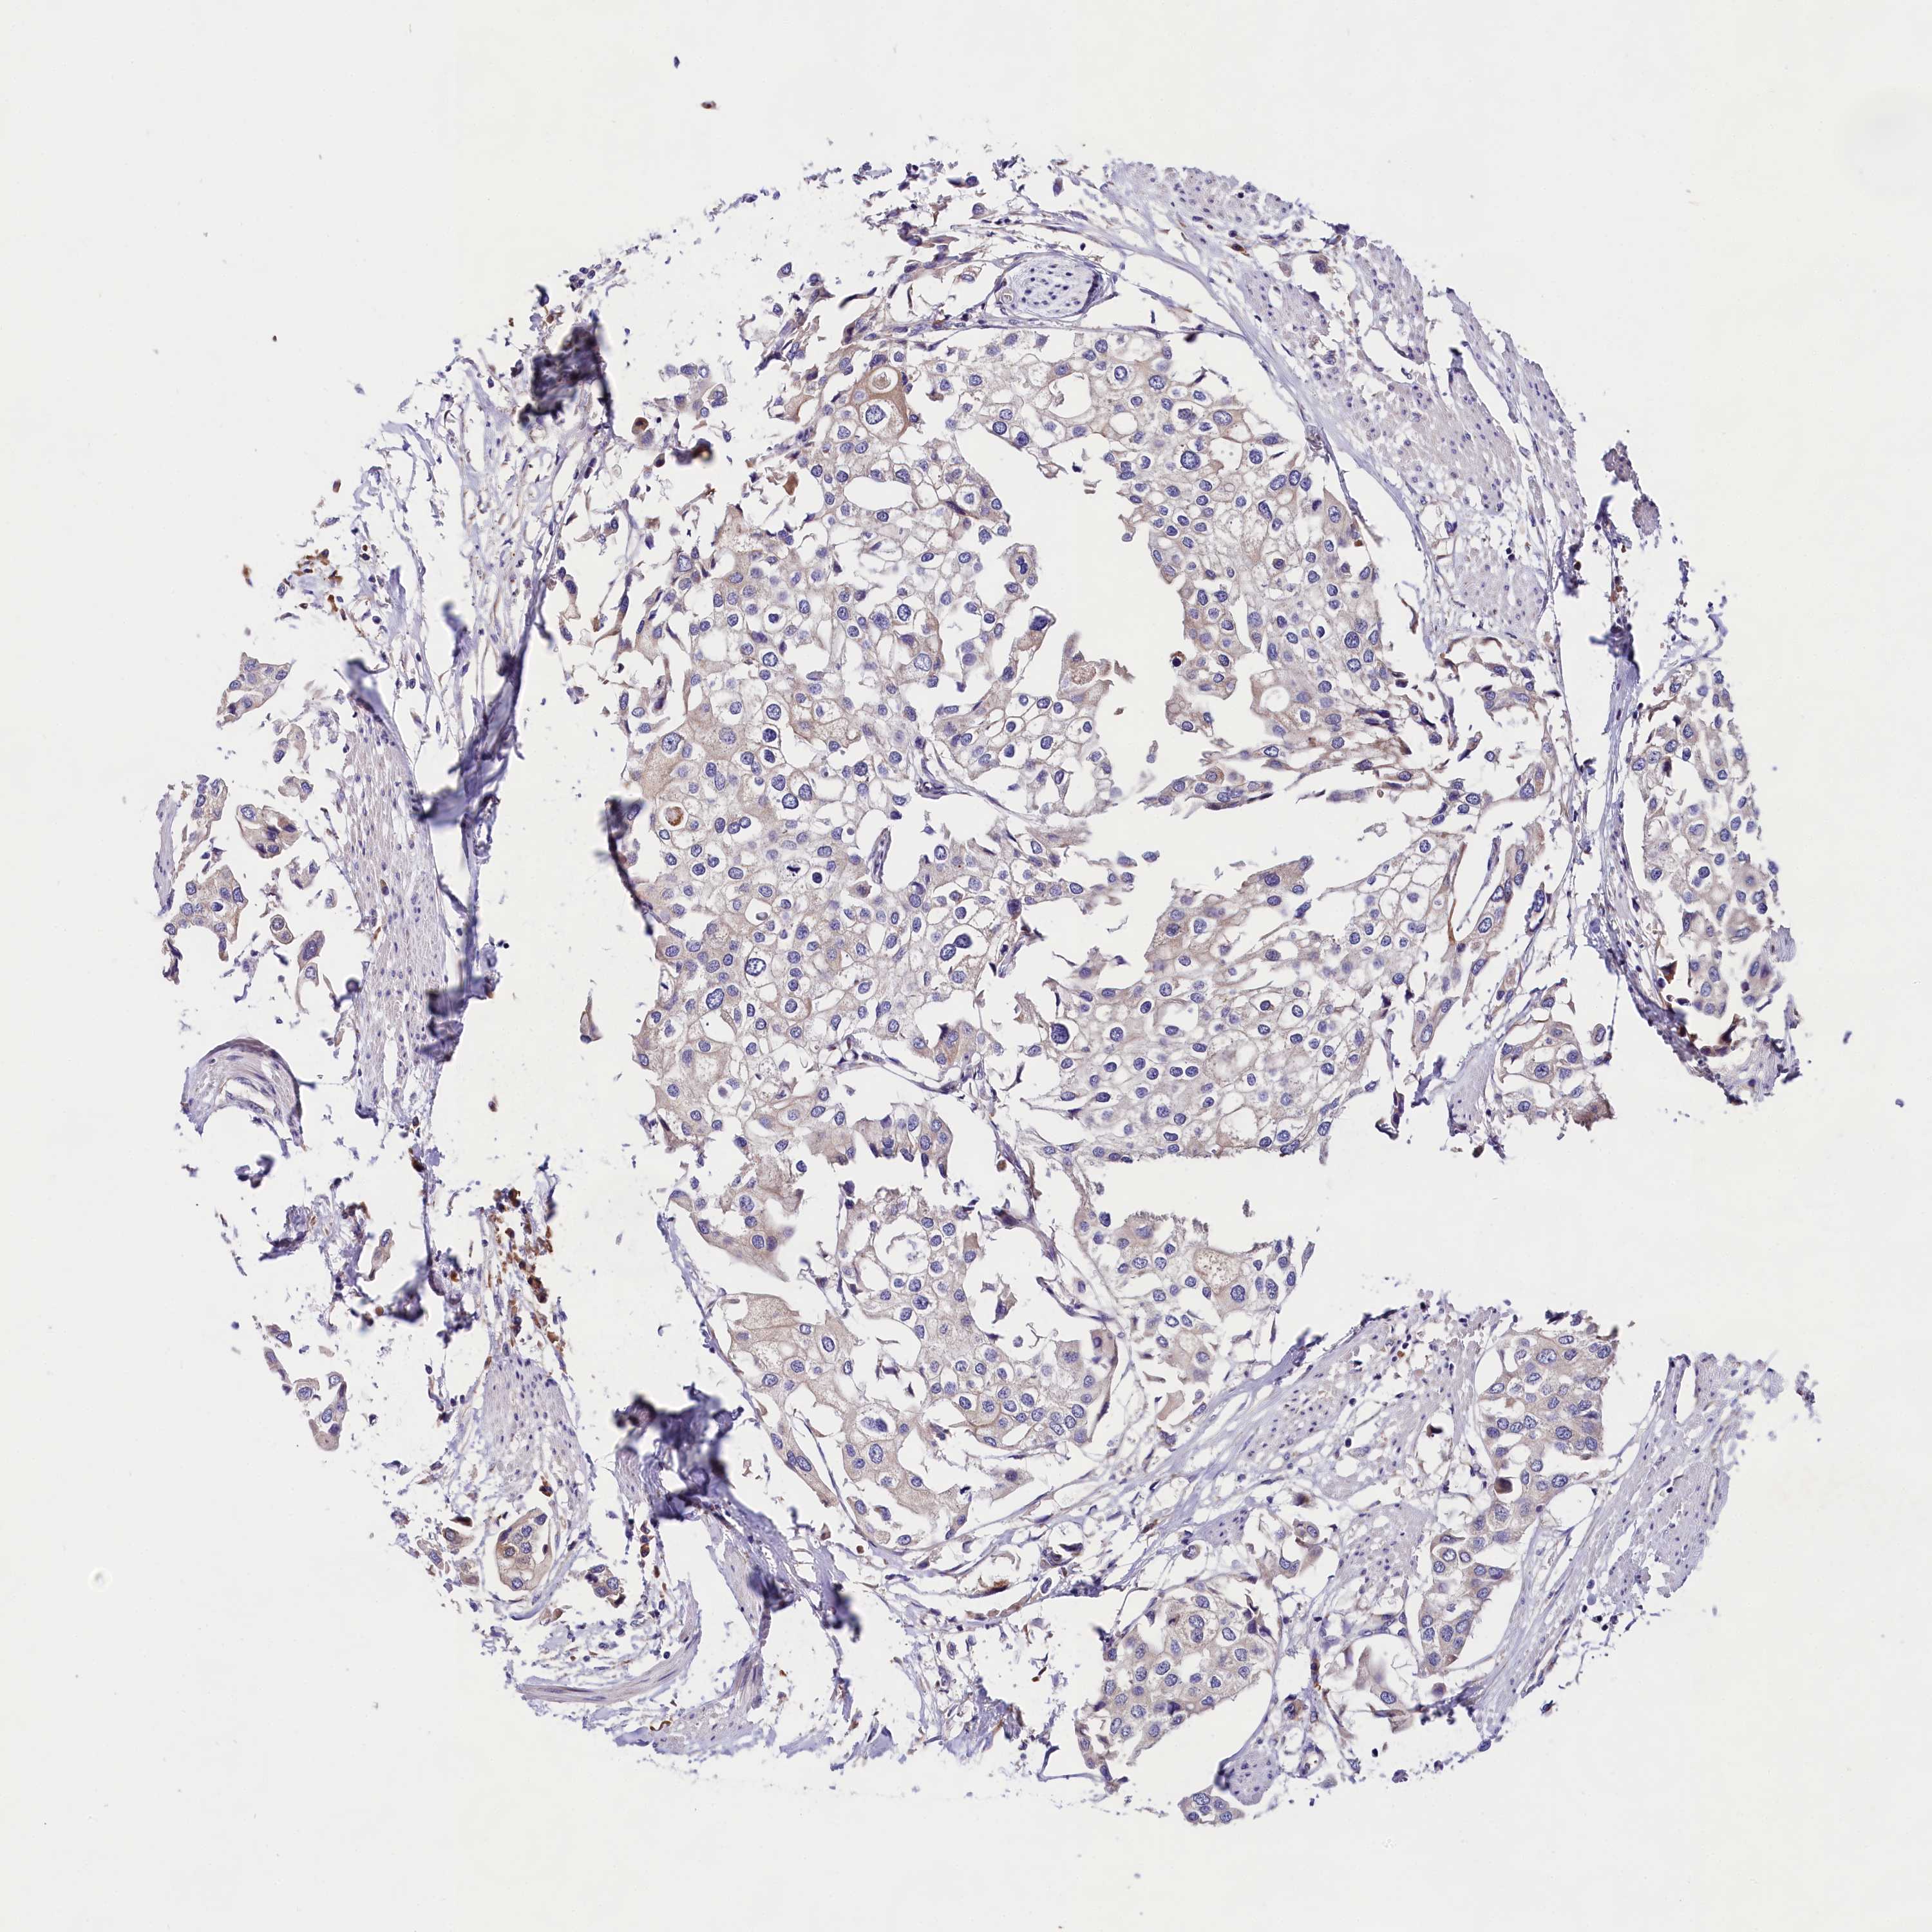

UROTHELIAL CANCER - Protein expressioni

A mouse-over function shows sample information and annotation data. Click on an image to view it in a full screen mode. Samples can be filtered based on level of antibody staining by selecting one or several of the following categories: high, medium, low and not detected. The assay and annotation is described here.

Note that samples used for immunohistochemistry by the Human Protein Atlas do not correspond to samples in the TCGA dataset.

Antibody stainingi

Antibody staining in the annotated cell types in the current human tissue is reported as not detected, low, medium, or high, based on conventional immunohistochemistry profiling in selected tissues. This score is based on the combination of the staining intensity and fraction of stained cells.

Each image is clickable and will lead to virtual microscopy that enables deeper exploration of all samples and also displays staining intensity scores, fraction scores and subcellular localization as well as patient and tissue information for each sample.

Antibody HPA040412

Antibody HPA040947

Urothelial carcinoma, High grade

Urothelial carcinoma, Low grade